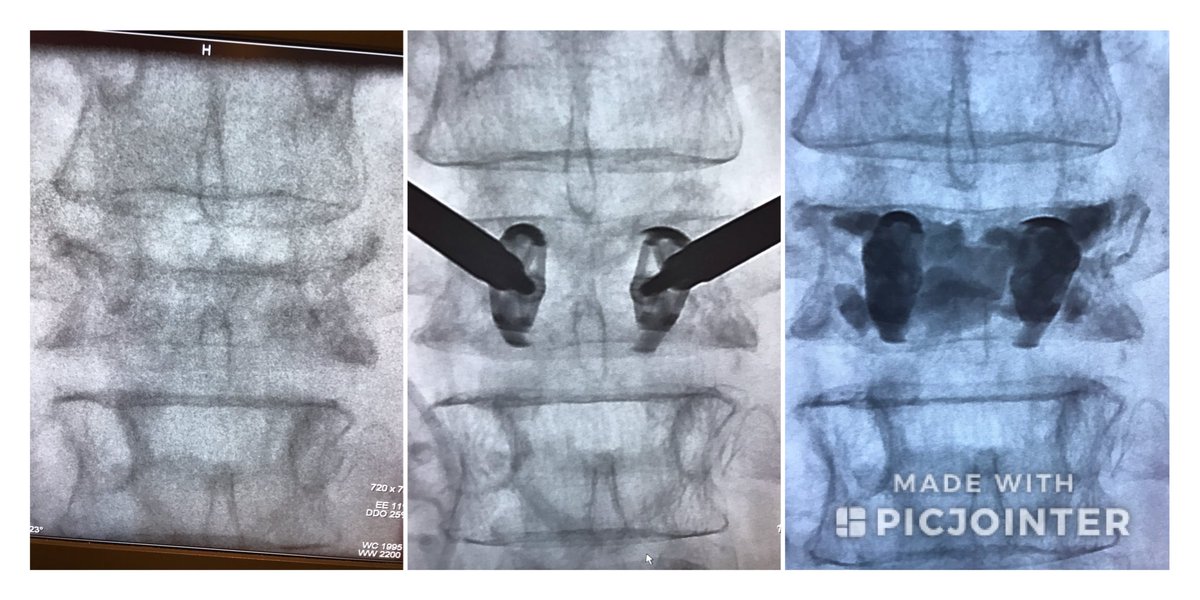

Stryker Spine Jack case at L4. First IR to place in Illinois! Patient feels great. Thanks to amazing Stryker support from Mike Villano. #Spinejack #jackit @mjvillano @Interventional2 #IRad #InterventionalRadiology #IamIR #IR #interventionalspine